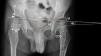

InstrumentosSe utilizaron distintas medidas radiológicas para cuantificar las variables (fig. 2):

Mediciones radiológicas realizadas: índice acetabular (IA), ángulo epifisario de Hilgenreiner (HE), ángulo acetábulo-epifisario (AE), ángulo cérvico-diafisario (CCD), línea de Hilgenreiner (H), línea de Perkins (P), longitud no cubierta de la cabeza femoral (A) y longitud total de la cabeza femoral (B).